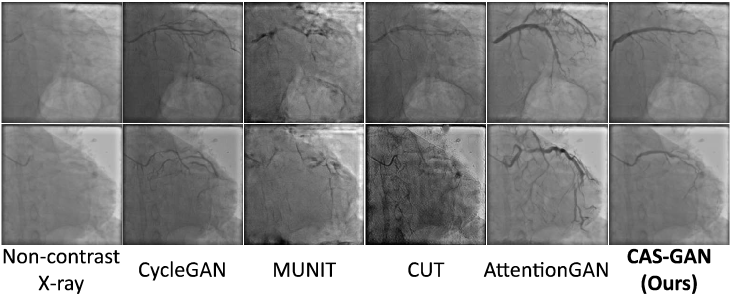

V-C External validation

We also conduct external validations to verify the generalization performance of different models. The data is derived from a collaborating hospital, consisting of 11 X-ray sequences from different patients. From each sequence, we extract two frames (before and after injecting contrast agents) to conduct experiments. Note that we directly evaluate models trained on the XCAD dataset without fine-tuning. Fig. 4 presents several qualitative results.

Despite all methods struggling with the significant variance between the XCAD and external datasets, CAS-GAN showcased relatively superior performance. The specialized design of our model, particularly its disentanglement approach, contributed to its better handling of the dataset’s challenges. In contrast, models like CycleGAN [11], MUNIT [41], and CUT [32] altered the image appearances significantly, while AttentionGAN [54] tended to generate unrealistic vessel structures, entangling with backgrounds. We anticipate that enhancing the dataset size and diversity will significantly improve model performance on external datasets and we will develop a more comprehensive dataset in future works.